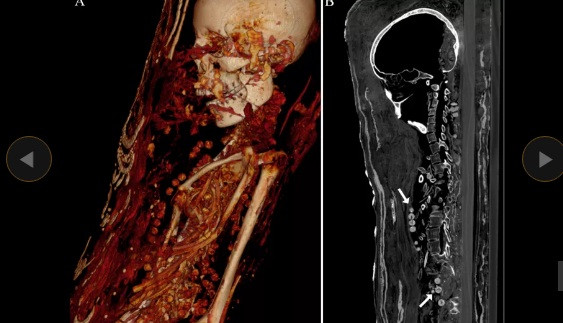

Các chuyên gia mới công bố thông tin đáng chú ý về 2 xác ướp được khai quật trong một ngôi mộ tại khu nghĩa địa cổ Saqqara, Ai Cập. Thay vì được đặt trong quan tài như nhiều trường hợp trước đó, hai xác ướp Ai Cập này được bảo quản theo cách đặc biệt.

Cụ thể, 2 xác ướp được quấn một lớp vải trước khi bao bọc bằng một lớp ván gỗ cực mỏng. Trên bề mặt của lớp ván gỗ là chân dung của người quá cố.

Thêm nữa, 2 xác ướp còn được trang trí bằng thạch cao và vàng. Nhà Ai Cập học Stephanie Zesch cho hay hai xác ướp gồm 1 nam và một nữ.

Kết quả kiểm tra cho thấy 2 xác ướp này qua đời vào khoảng năm 30 trước Công nguyên đến năm 395 sau Công nguyên.

Hai người này qua đời khi còn khá trẻ. Trong khi người đàn ông cao 1,64m qua đời khi khoảng 25 - 30 tuổi thì người phụ nữ có chiều cao 1,56m chết khi 30 - 40 tuổi.